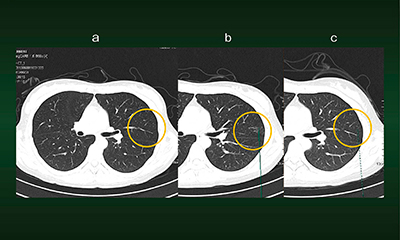

症例2は,47歳,女性。結節性病変の経過観察中に,CTにてすりガラス状陰影が認められた(図3 b)。病変にマーキングをすると,過去の同じ断面の画像が表示され(図3 c),3か月後のフォローアップの際にも同様に表示される(図3 a)。同じ断面の画像が並列表示されるため,病変の変化が簡単に観察可能である。病変にマーキングさえしておけば,比較するべき部位が位置合わせされた状態で瞬時に表示されることも,syngo.viaの特長である。

図3 症例2:Lung CAREによる経時的画像比較